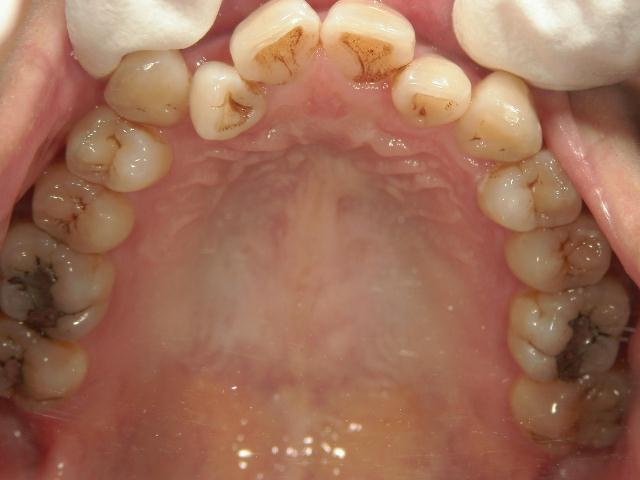

アクアシステム(透明マウスピース矯正)/上下顎 症例(8)

43歳 女性 浜松市中区在住 治療期間2年

(上顎の治療終了後、下顎の治療を開始)

矯正歯科 治療前 上顎